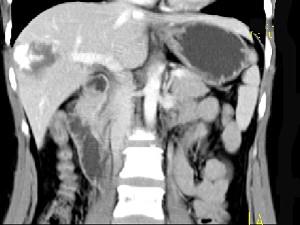

问题 女,38岁,无任何症状,体检发现肝右叶占位性病变,增强表现如图,最可能的诊断为 ( )

选项 A、肝脓肿 B、肝腺瘤 C、肝转移瘤 D、肝血管瘤 E、原发性肝癌

答案 D